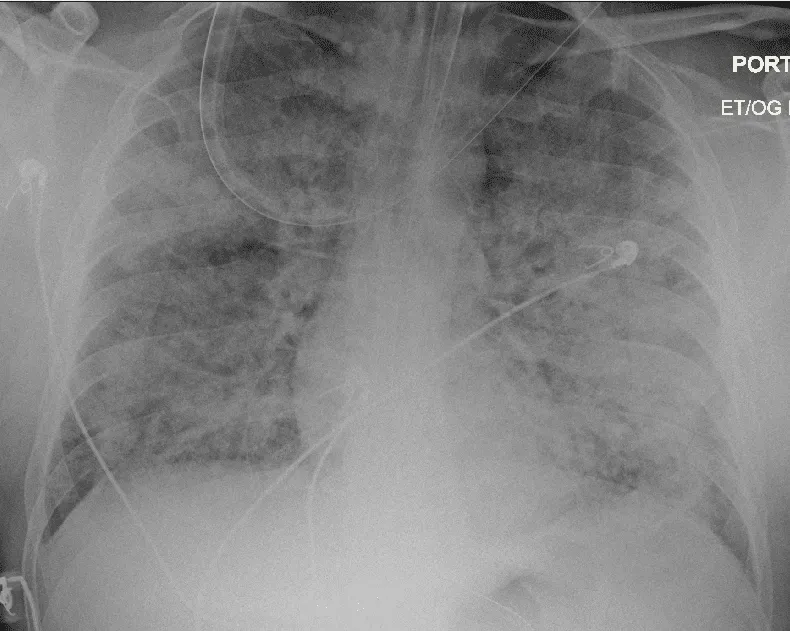

(1) 2차 세균성 폐렴 (Secondary Bacterial Pneumonia)

인플루엔자 바이러스는 상기도 점막의 방어력을 약화시켜 폐렴구균, 황색포도상구균 등의 이차 감염이 발생할 위험을 높입니다.

특히 65세 이상 고령자와 만성 폐질환자에서는 폐렴으로 인한 입원이 흔하며, 미국 CDC 자료에 따르면 인플루엔자 관련 사망자의 상당수가 폐렴 합병증과 연관되어 있습니다[1].

(2) 급성 호흡부전 및 입원 치료 필요

바이러스 감염이 폐로 확산되며 급성 호흡곤란 증후군(ARDS)이나 산소포화도 저하로 이어질 수 있습니다. 이러한 경우에는 고농도 산소 요법 또는 인공호흡기 치료가 필요할 수 있습니다.